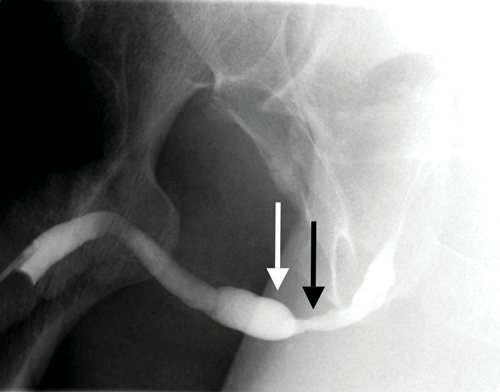

In the anterior urethra, strictures are more common in the bulbous portion of the urethra [7] (Figure 8 and 9).

Figure 8: A good volume of contrast has been inserted to ensure a stricture is not overcalled.

A persistent stricture is identified in the bulbous urethra (black arrow) with proximal dilatation (white arrow).

Figure 9: Persistent stricture seen within the penile urethra (arrow) in a patient with previous urethroplasty.

The proximal penile urethra and bulbous urethra are dilated and lobular.